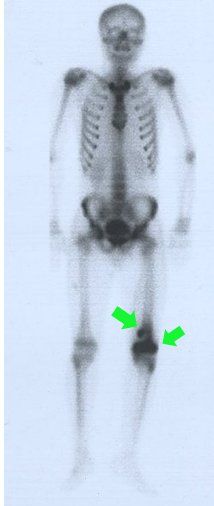

Bone scintigraphy is also a method that is used from time to time. Here, the bone content of the whole body is revealed. The purpose here is; It is to understand whether the mass has spread to other bones and to give an idea about whether the mass is benign or malignant (pic-29).